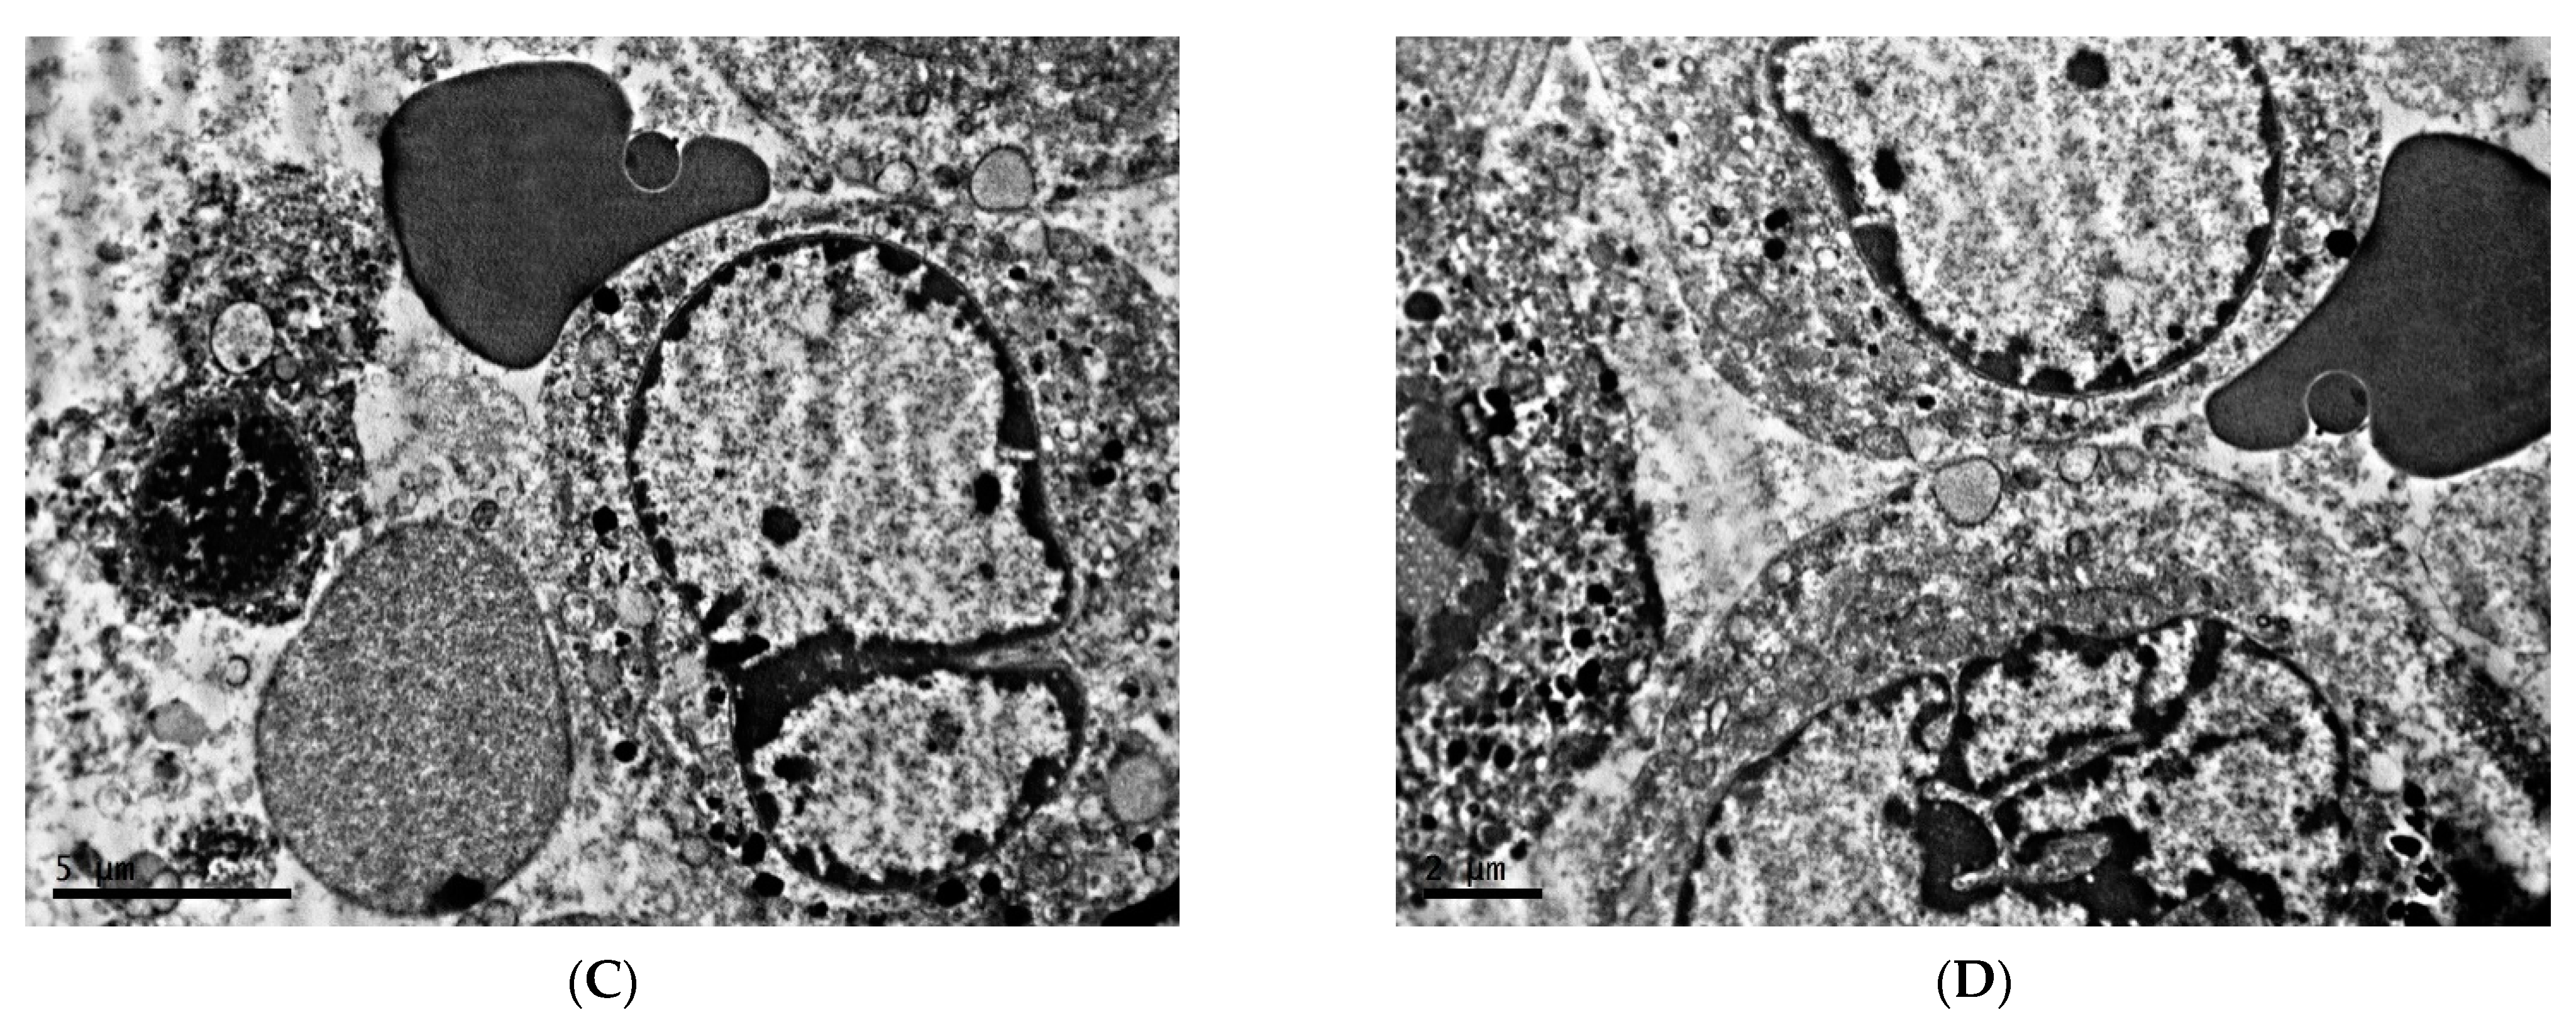

2.2. Ultrastructure of Transplantable Malignant Melanoma B16 in Conditions of Constant Lighting Regime